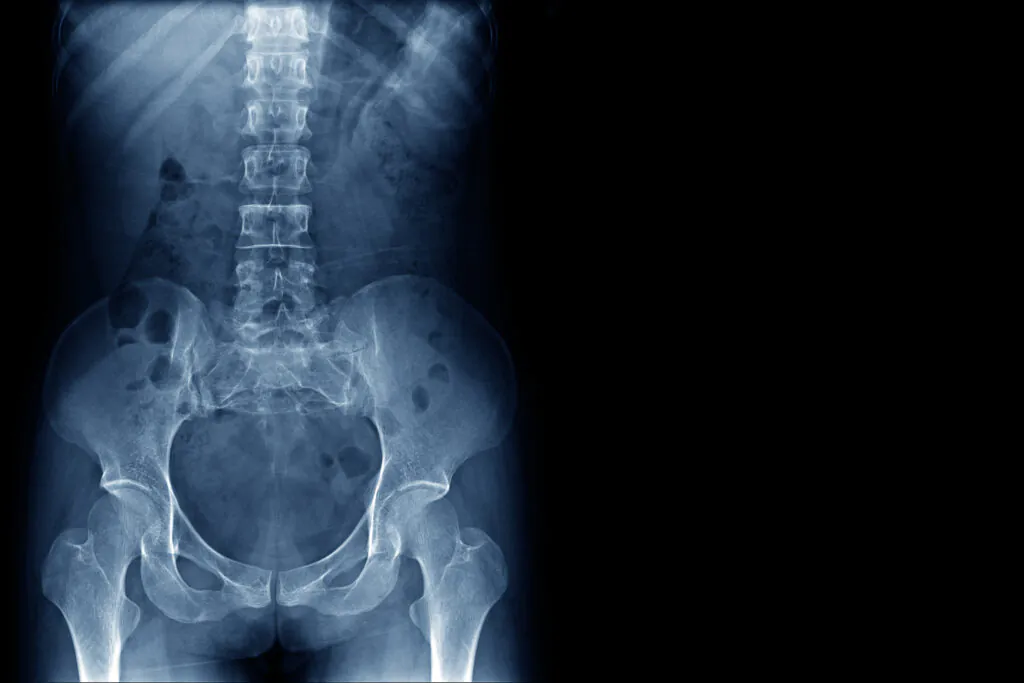

Regarding diagnostic tests and imaging, clinical practice guidelines from major organizations strongly recommend against routine use of X-rays, MRIs, or CT scans in the first several weeks of nonspecific lower back pain because early imaging does not improve outcomes and may lead to unnecessary procedures on incidental findings.8  Instead, these tests are reserved for cases with red flags or when symptoms persist despite conservative management, or when surgical or invasive procedures are being considered.

PTs evaluate lower back pain through a comprehensive history and physical examination, including inspection and palpation of the back, assessment of range of motion (ROM) and muscle strength, provocation tests (such as straight-leg raising to assess nerve involvement), and a focused neurologic exam to check reflexes, sensation, and strength in the lower extremities This thorough clinical assessment helps PTs identify mechanical or movement-related contributors to pain and dysfunction, tailor individualized treatment plans, and determine whether further medical evaluation or imaging may be necessary.